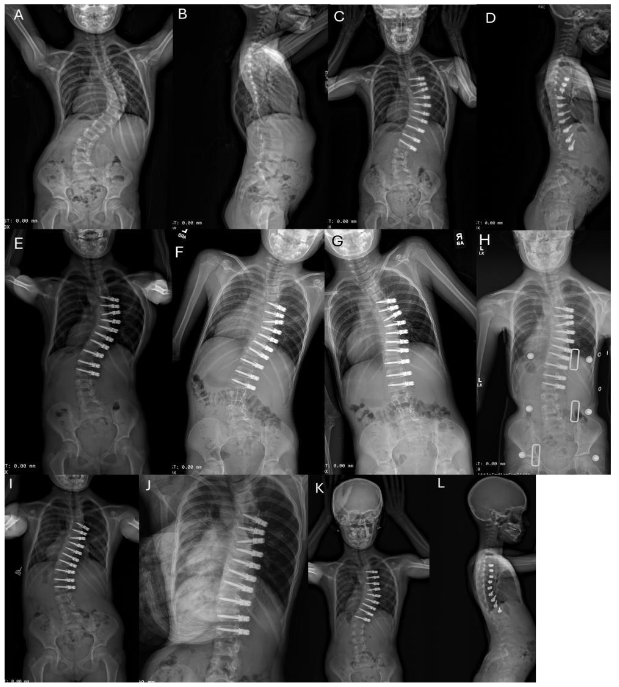

Fig. 2A-L. Example of unilateral thoracic ASC with intervertebral de-tethering releases.